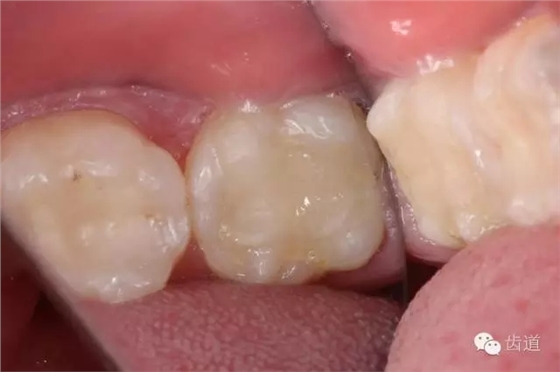

檢查:術(shù)后半年回訪,37牙體及合面嵌體未見缺損及裂紋,邊緣密合,未探及繼發(fā)齲,探痛-,叩痛-,松動(dòng)-,冷水刺激痛-,未探及牙周袋及附著喪失,牙齦無紅腫,X線片檢查示根尖周膜連續(xù)性恢復(fù),根尖周透射影消失。

1. 術(shù)后半年口內(nèi)照片